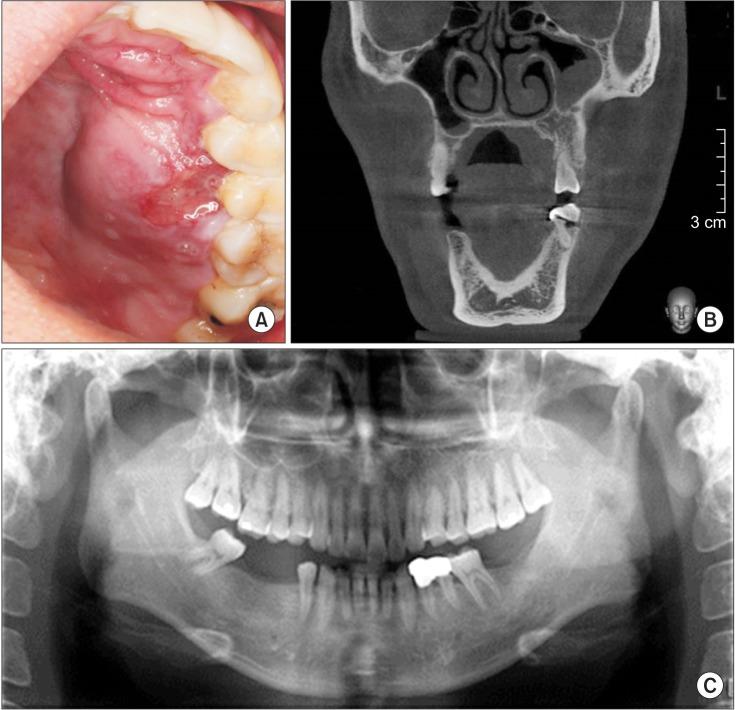

Angiography is the gold standard for the diagnosis and complete resection of arteriovenous malformations (AVMs). The absence of residual AVM after surgery is commonly believed to reduce the risk of future hemorrhage. However, AVMs can recur after proven complete angiographic resection can occur, albeit rarely, especially in the pediatric population. We report a rare case of a recurrent AVM two years after complete resection in an adult patient. This case report shows that AVMs in adults can recur despite their rarity and despite postoperative angiography confirming complete removal. Moreover, in this case, the recurrent AVM involved a new feeding vessel that was not involved with the initial lesion.

血管造影是诊断和完整切除动静脉畸形(AVM)的金标准。通常认为手术后无残留AVM可降低未来出血的风险。然而,尽管血管造影已证实完全切除,但AVM仍可能复发,尽管这种情况很少见,尤其是在儿科人群中。我们报告了一例成年患者在完全切除后两年复发AVM的罕见病例。本病例报告表明,尽管成人AVM复发罕见且术后血管造影证实已完全切除,但仍可复发。此外,在本病例中,复发性AVM涉及一条与初始病变无关的新供血血管。